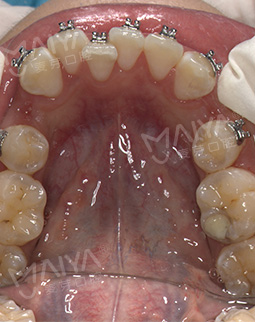

摘牙套前最后的一次拍照了,先看看牙,整齐啦!医生说等完全排齐后我就直接可以脱掉这些金属的东西了,想想好开心,吃盘龙虾奖励自己~~

2017/03/17 矫正过程中